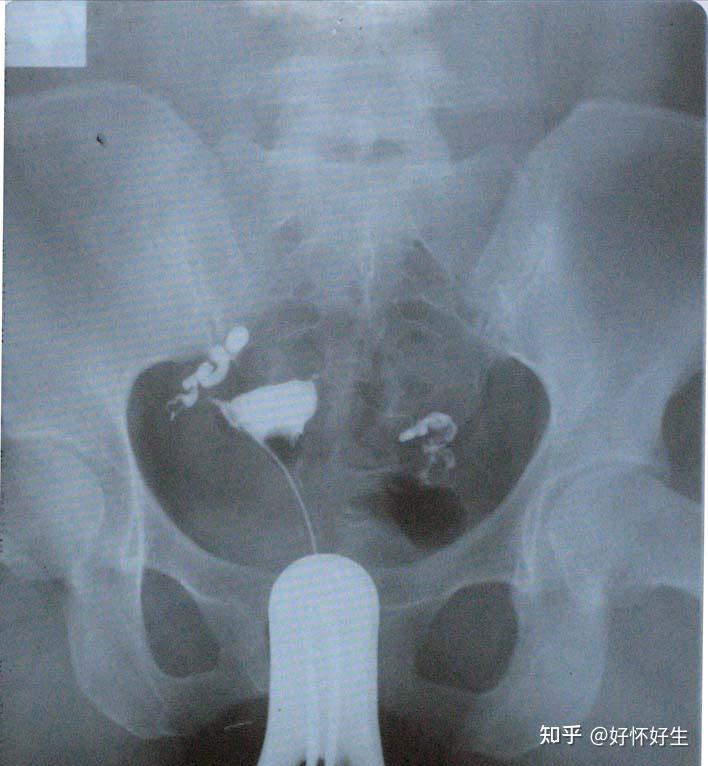

其中就有一種特別的什切輸卵狀況,即輸卵管阻塞合并輸卵管水腫(積水)時,掉/醫生會建議先把有問題的結扎輸卵管先做切除或結扎后再進行試管嬰兒。

輸卵管水腫,顧名思義就是輸卵管阻塞后,它所產生的分泌物無法排出而累積在輸管腔內,久而久之就造成了輸卵管整條腫大(可以把它想像成一條香腸樣)。

而這些液體中常常都含有大量的發炎物質、細菌、壞死的細胞等對胚胎生長不利的成分。因為輸卵管末端已經阻塞,所以這些不好的東西的流動方向就僅能往子宮腔內,造成胚胎著床及發育的影響。

輸卵管水腫手術治療方式目前有兩種。第一種是把水腫那側整條輸卵管以微創內視鏡切除;另一種是把水腫那側輸卵管和子宮連接處用內視鏡手術阻斷/結扎。